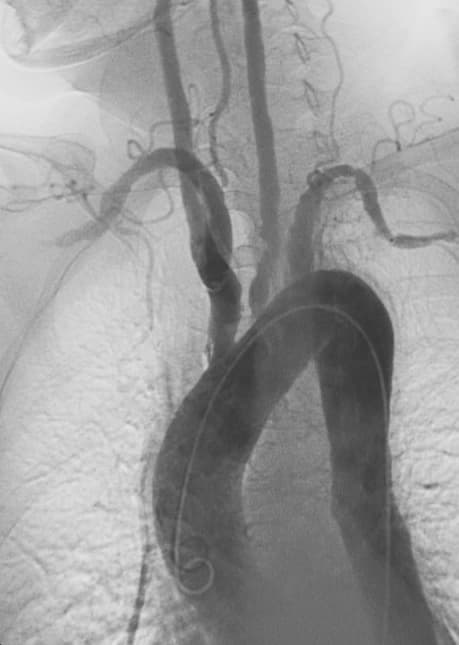

Takayasu's arteritis (TA), also known as aortic arch syndrome, nonspecific aortoarteritis, and pulseless disease, is a form of large vessel granulomatous vasculitis with massive intimal fibrosis and vascular narrowing, most commonly affecting young or middle-aged women of Asian descent, though anyone can be affected. It mainly affects the aorta (the main blood vessel leaving the heart) and its branches, as well as the pulmonary arteries. Females are about 8–9 times more likely to be affected than males. Those with the disease often notice symptoms between 15 and 30 years of age. In the Western world, atherosclerosis is a more frequent cause of obstruction of the aortic arch vessels than Takayasu's arteritis. Takayasu's arteritis is similar to other forms of vasculitis, including giant cell arteritis which typically affects older individuals. Due to obstruction of the main branches of the aorta, including the left common carotid artery, the brachiocephalic artery, and the left subclavian artery, Takayasu's arteritis can present as pulseless upper extremities (arms, hands, and wrists with weak or absent pulses on the physical examination) which may be why it is also commonly referred to as the "pulseless disease." Involvement of renal arteries may lead to a presentation of renovascular hypertension. Some people develop an initial "inflammatory phase" characterized by systemic illness with signs and symptoms of malaise, fever, night sweats, weight loss, joint pain, fatigue, and fainting. Fainting may result from subclavian steal syndrome or carotid sinus hypersensitivity. There is also often anemia and marked elevation of the ESR or C-reactive protein (nonspecific markers of inflammation). The initial "inflammatory phase" is often followed by a secondary "pulseless phase". The "pulseless phase" is characterized by vascular insufficiency from intimal narrowing of the vessels manifesting as arm or leg claudication, renal artery stenosis causing hypertension, and neurological manifestations due to decreased blood flow to the brain.